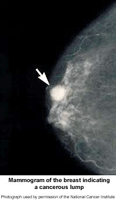

Picture of mammogram of the breast indicating a cancerous lump